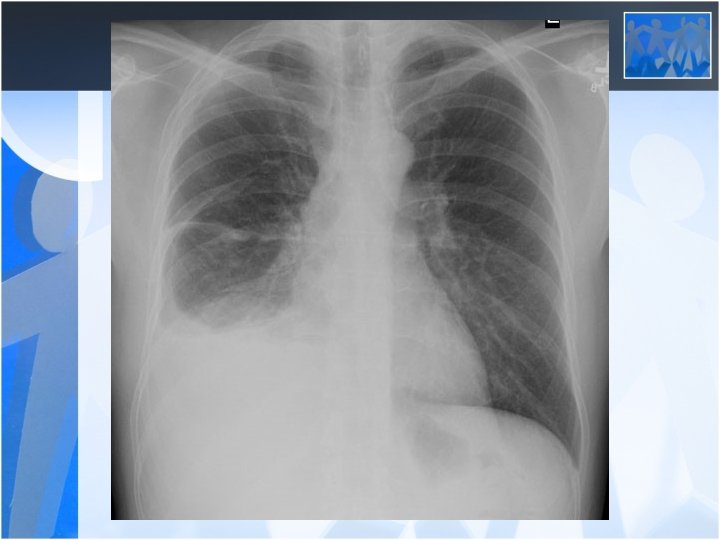

• The most common clinical presentations are dyspnea, chest pain, unilateral decreased volume of the affected hemithorax (frozen chest) • Nodular thickening of the pleura, irregular thickening of the interlobar fissure, absence of mediastinal shift with massive pleural effusion (frozen chest) • Diagnosis by histologic examination • Treatment oncologic and surgical if possible, prognosis is poor